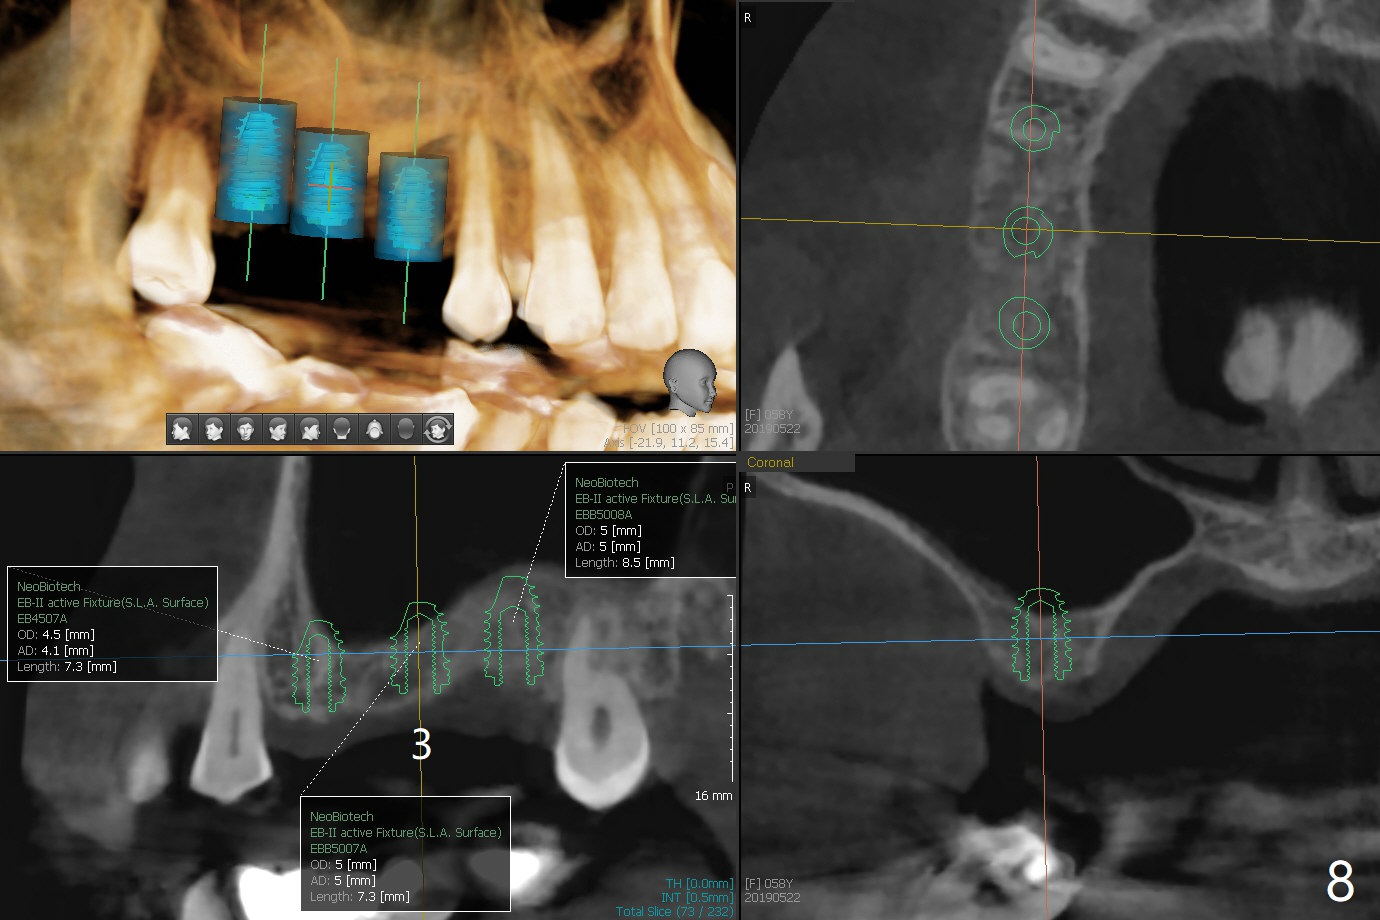

A 57-year-old woman returns with pain in the upper right quadrant (Fig.1,2). In fact the mesiobuccal root of the tooth #2 has vertical fracture. Although the socket destruction at #3 is not as extensive as that of #2, the socket of #3 has communication with the sinus. Prior to socket preservation, a piece of Osteogen plug is inserted at #3. PRF should be prepared for severe bone loss. In contrast there is no bone loss around the implants at #19 or #30 (Fig.1,3,4). Although the socket at #2 is slightly open 9 days postop, bone graft appears to be present (Fig.5). The bone at #2 and 3 seems to regenerate 7 months post socket preservation (Fig.6). Three short implants seem to be better than 2 implants for 3-unit FPD (Fig.7-9).